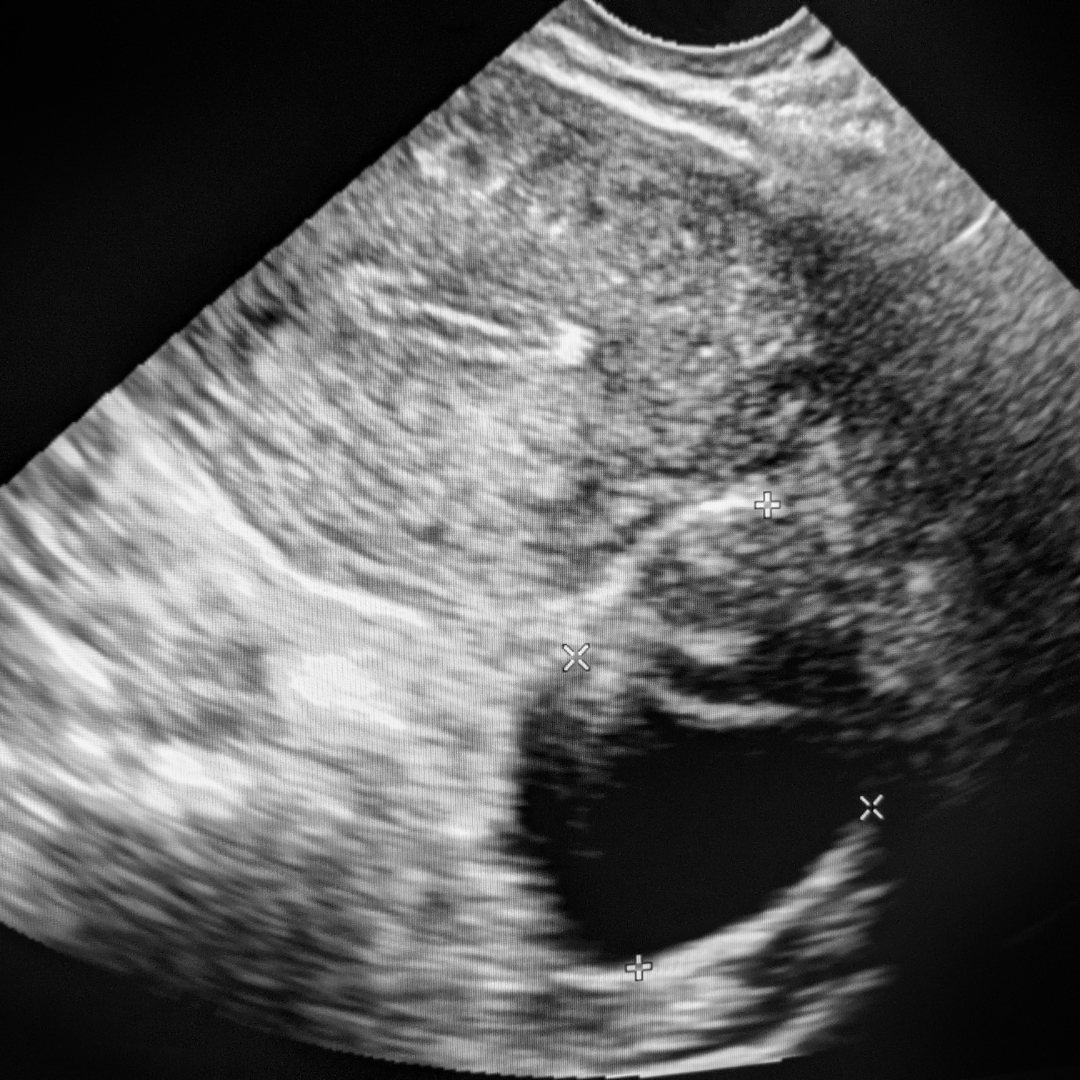

Meme Kisti Görüntüleri ve Ultrason

Meme kisti ultrasonda nasıl görülür sorusu, görüntüleme raporunu okuyan hastaların en çok merak ettiği başlıklardan biridir. Ultrason incelemesinde meme kisti genellikle anekoik (siyah), düzgün sınırlı ve arka akustik güçlenmesi olan bir odak şeklinde izlenir.

Bu bulgular, en sık karşılaşılan ve iyi huylu kabul edilen basit meme kisti ile uyumludur.

Basit meme kisti saptandığında çoğu zaman ek bir işleme gerek kalmadan takip önerilir.

Meme kisti içeriği yoğun olan durumlarda ultrason görünümü farklılık gösterir.

Meme kisti içerisinde iç yansımalar, tortu, hafif bulanıklık veya duvar kalınlaşması görülmesi, kistin komplike ya da kompleks meme kisti olabileceğini düşündürür. Bu ayrım oldukça önemlidir çünkü bu tip meme kistlerinde izlem aralığı kısalabilir ya da ileri değerlendirme gerekebilir.

Ultrason bulguları, meme kistinin yapısal özelliklerini netleştirmede temel rol oynar.

Meme kisti anekoik kist nedir sorusuna gelince; “anekoik” terimi, ses dalgasını yansıtmayan ve tamamen sıvı içerikli yapıyı ifade eder. Anekoik meme kisti çoğunlukla iyi huyludur ve kansere dönüşüm riski beklenmez. Ancak her meme kisti ultrason raporunda BI-RADS kategorisi ile birlikte değerlendirilir ve klinik bulgularla birlikte yorumlanır.